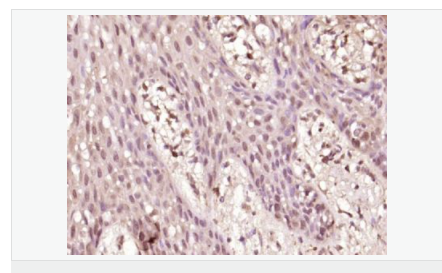

| 产品应用 | WB=1:500-2000 ELISA=1:5000-10000 IHC-P=1:100-500 IHC-F=1:100-500 Flow-Cyt=1μg /test IF=1:100-500 (石蜡切片需做抗原修复) not yet tested in other applications. optimal dilutions/concentrations should be determined by the end user. |